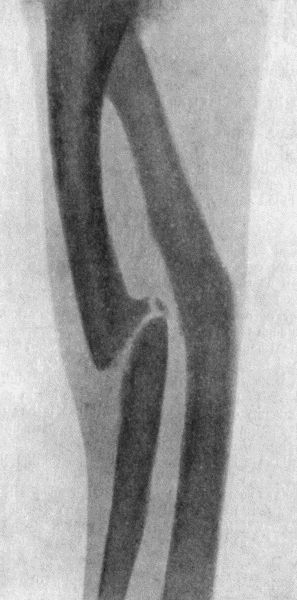

Fig. 3.—Showing (1) Oblique fracture of Tibia; (2)

Oblique fracture with partial separation of Epiphysis of upper end of

Fibula; (3) Incomplete fracture of Fibula in upper third. Result of

railway accident. Boy æt. 16.

(2) According to the Direction of the Break.—Transverse fractures are those in which the bone gives way more or less exactly at right angles to its long axis. These usually result from direct violence or from end-to-end pressure. Longitudinal fractures extending the greater part of the length of a long bone are exceedingly rare. Oblique fractures are common, and result usually from indirect violence, bending, or torsion (Fig. 3). Spiral fractures result from forcible torsion of a long bone, and are met with most frequently in the tibia, femur, and humerus.